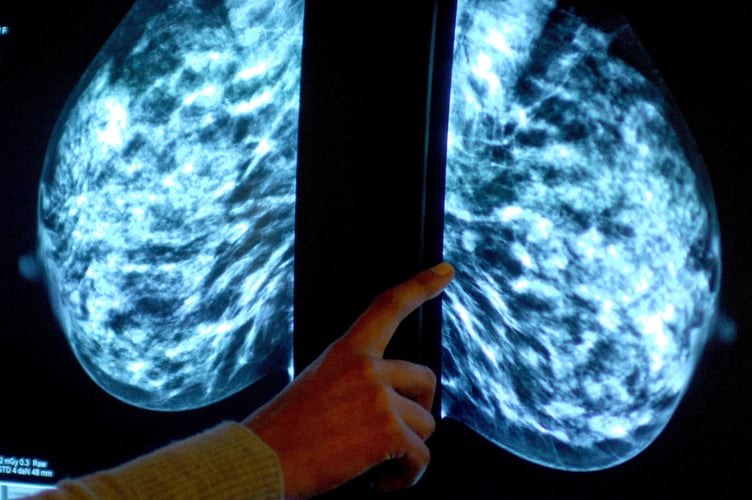

Breast screening uptake in Gloucestershire remains below pre-pandemic levels, new figures show.

NHS England figures show 25,125 of the 36,155 people invited for a screening in the former NHS Gloucestershire CCG had a test in the year to March this year.

It meant uptake of the screening stood at 69% – roughly in line the year before, but below pre-pandemic levels of 75% in 2019-20.

The figures show breast screening uptake across England increased to 65% last year from 63% in 2021-22. However, it remained well below pre-pandemic levels when 70% was recorded.